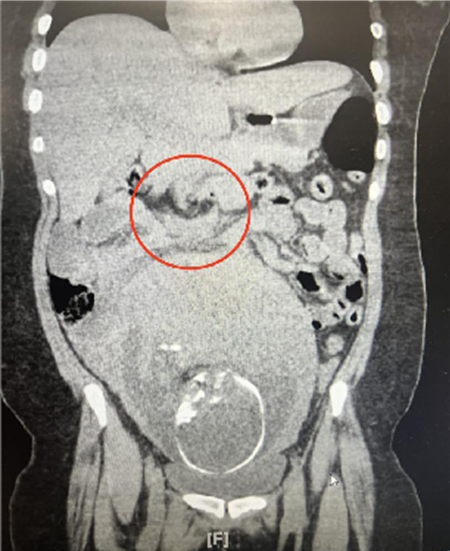

The patient was initially administered intravenous fluids and morphine. Laboratory studies and an ultrasound of the abdomen and kidneys were obtained to evaluate the patient’s flank pain; both were unremarkable. After several hours of monitoring, the patient endorsed no improvement in pain and non-contrast CT of the abdomen and pelvis was performed. Imaging was negative for nephrolithiasis and other renal pathology. Appendix appeared normal without signs of inflammation or enlargement. However, study was significant for a dilated loop of small bowel in the right mid abdomen, laterally, with significant adjacent mesenteric edema. There is swirling of mesenteric pedicle with no visualization of the superior mesenteric vein distal to the area of swirling and focal tapering of the superior mesenteric artery. Findings are suspicious for small bowel volvulus or internal hernia with concern for small bowel mesenteric/bowel ischemia, Figure 1. General Surgery consultation and evaluation advised immediate surgical management. The patient underwent diagnostic laparoscopy; an internal hernia was identified and reduced, and Petersen’s space was surgically closed. The patient’s postoperative course was unremarkable, and she underwent an uncomplicated scheduled repeat cesarean section at term.

Figure 1 There is a dilated loop of small bowel in the right mid abdomen, laterally with significant adjacent mesenteric edema. There is swirling of mesenteric pedicle with no visualization of the superior mesenteric vein distal to the area of swirling and focal tapering of the superior mesenteric artery.